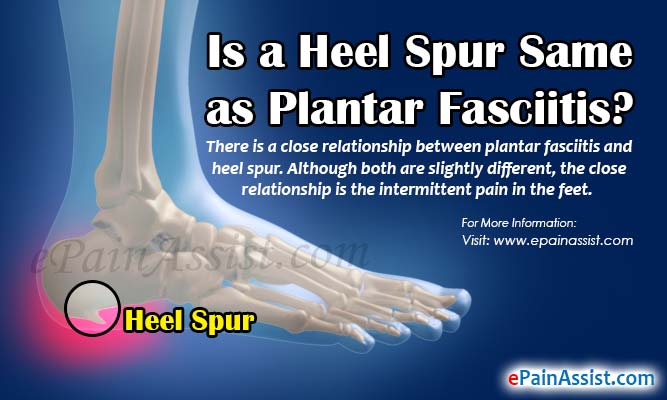

Heel Spur - Heel Pain Institute of  Is a Heel Spur Same as Plantar

Is a Heel Spur Same as Plantar  heels… | Heel spurs, Heel spurs

Heel Spur Pain Also Called Calcaneal  Heel Spur VS Plantar Fasciitis

Heel Spur VS Plantar Fasciitis  10 Heel Pain Causes And When To See a